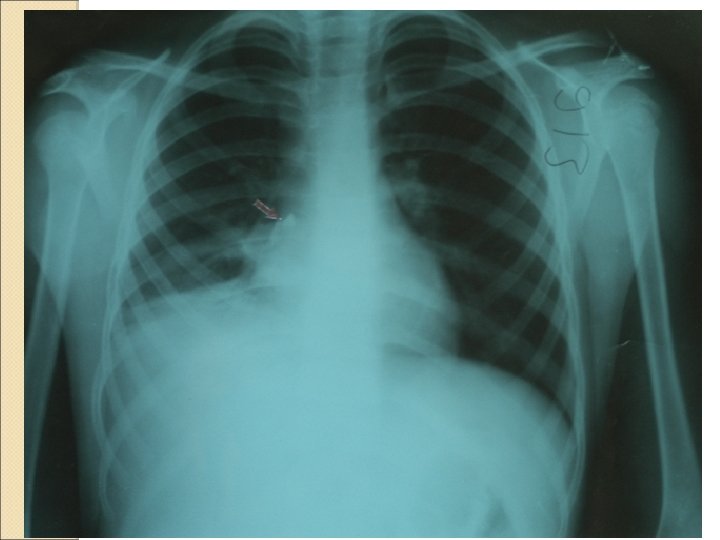

Laboratory findings Most infants with a single episode of wheezing will not require a chest radiograph, other than to confirm positive additional findings and/or to alleviate parental anxieties Any child with recurrent episodes of wheezing or congenital anomalies should have anteroposterior and lateral radiographic views taken to ascertain the presence of hyperinflation and/or structural abnormalities Suspicion of structural abnormalities may warrant additional imaging studies such as a CT or MRI and/or direct visualization using laryngobronchoscopy

Primer siliyer diskinezi- pnömotoraks